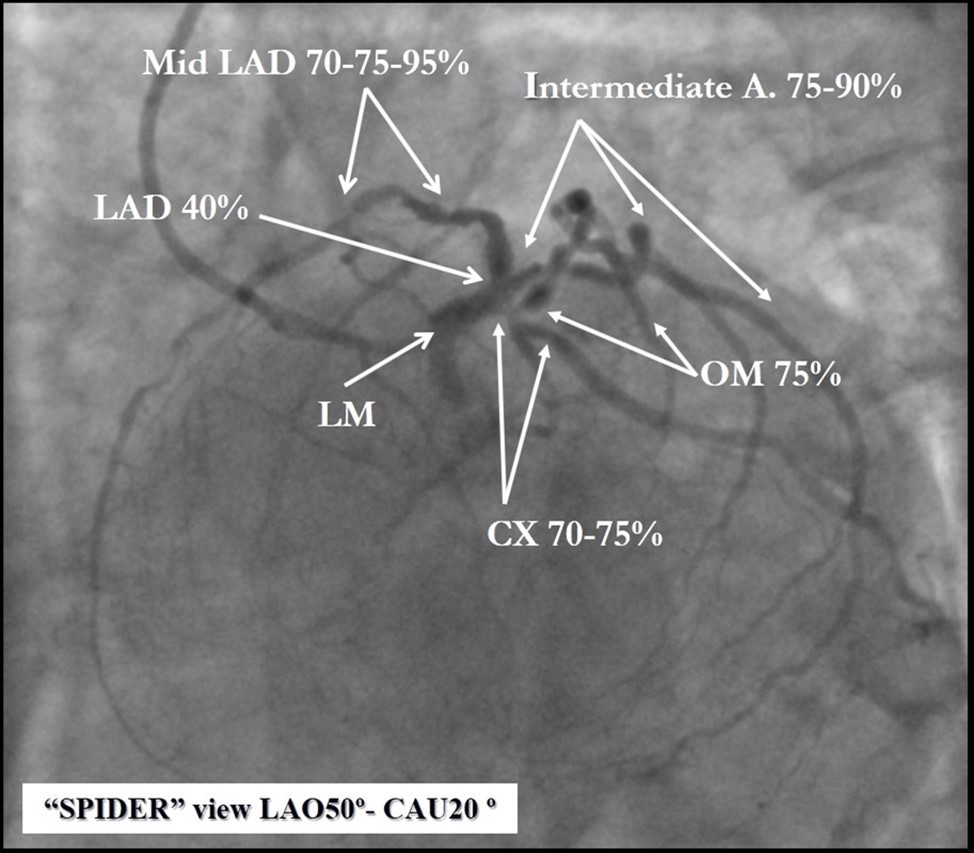

Angiography revealed rare anatomical variation LMCA quadrifurcation (Figure 1, Figure 2), 50% stenosis of the distal part of the LMCA, 40% stenosis of the ostial segment of left anterior descending (LAD) artery and diffuse prolonged 70-75-95% stenosis in mid-segment (Figure 3), 75% stenosis of the ostial segment of the circumflex (CX) artery, 75% stenosis of the ostial segment of the first marginal branch (OM1), 75-90% stenosis of the proximal segment of the intermediate artery (IMA), prolonged diffuse severe 90-95% stenosis of mid-segment of the right coronary artery (RCA) (Figure 4).

Figure 1.Quadrifurcation of the left main coronary artery

Figure 2.Schematic presentation of the left main quadrifurcation.